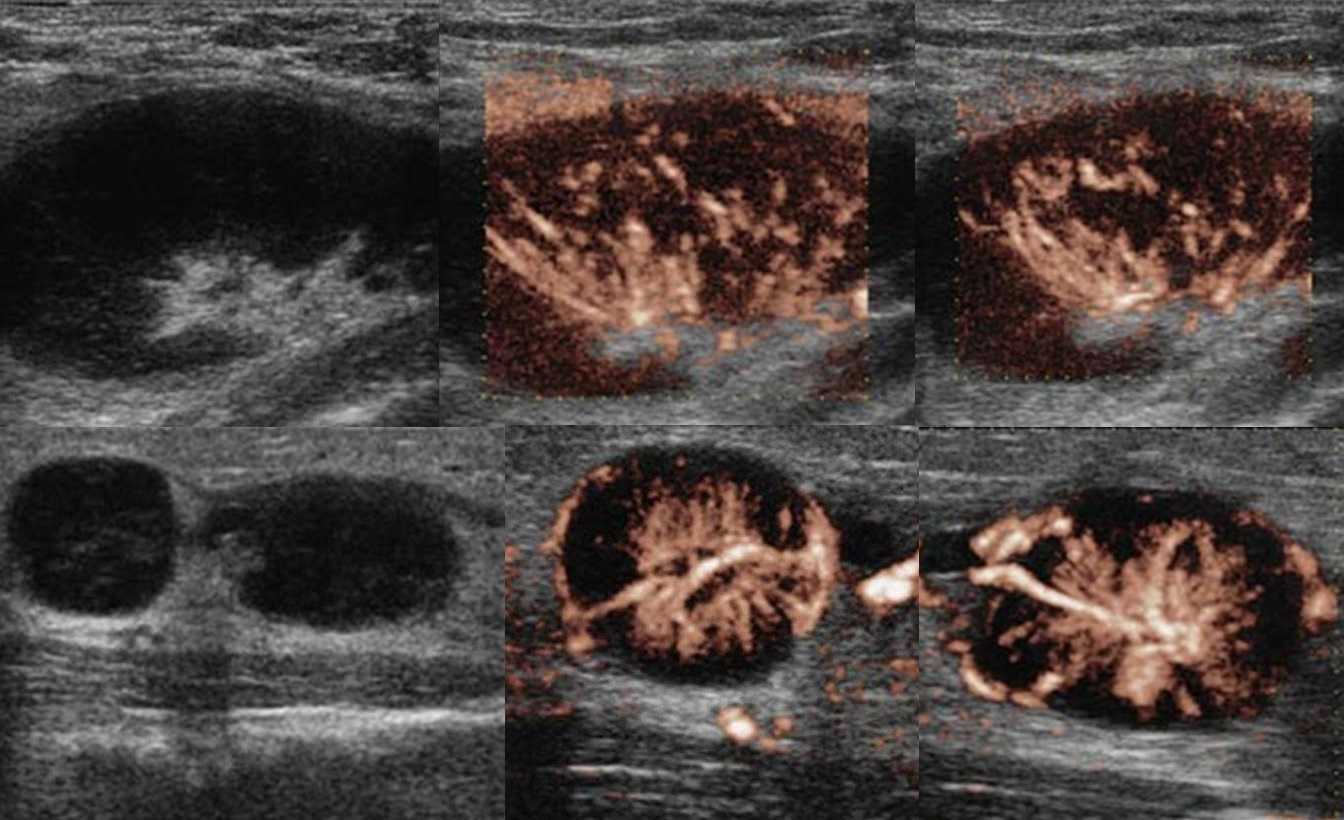

Рисунок. На УЗИ лимфоузлы увеличены, овальной формы, четкий и ровный контур, эхогенность пониженная, корковая зона несколько расширена, центральный рубчик видно отчетливо; кровоток в воротах усилен, сосуды расположены правильно — расходятся радиально, подкапсульный кровоток не определяется. Заключение: Лимфаденопатия с признаками высокой степени активности.

Рисунок. Женщина жалуется на «опухоль» в подмышке и на локте. Неделю назад повздорила с соседской кошкой. На УЗИ подмышечный (сверху) и локтевые (снизу) лимфоузлы увеличены, округлой формы, выраженная гиперплазия корковой и околокорковой зоны, гиперэхогенный центральный рубчик сохранен; кровоток заметно усилен, сосуды расположены правильно — радиально. Заключение: Лимфаденопатия с признаками высокой степени активности. При болезни кошачьей царапины на месте укуса или царапины образуются небольшие гнойнички и одновременно воспаляются близкие лимфоузлы. Один или группа лимфоузлов увеличиваются в размерах до 5-10 см, становятся болезненными, уплотняются. Через 2-4 недели происходит самоизлечение. Иногда образуются абсцессы и свищи.